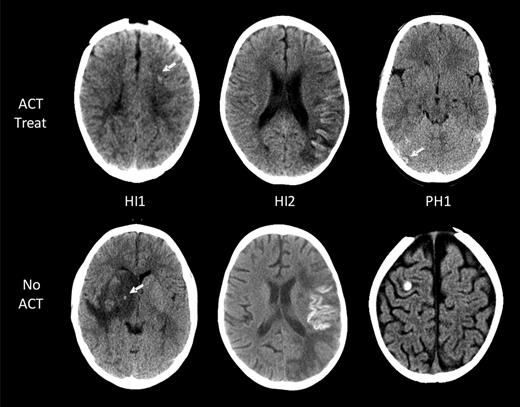

ICH in children with AIS. Intracranial hemorrhages are classified according to the ECASS grading system. Representative examples of the 3 grades encountered (HI1, HI2, and PH1) are shown for both children on ACT (top row) and those not on ACT (bottom row). No larger hematomas or ECASS PH2 were observed in the ACT-treated group. White arrows point at areas of ICH.

Radiologic data included number and location of infarcts (vascular territory, brain structures, and laterality) and presence of ICH, including hemorrhagic conversion of infarcts at AIS diagnosis and during ACT. For every child with ACT-associated ICH, all brain imaging studies were re-evaluated by the study pediatric neuroradiologist (S.L.) and a pediatric neurologist (A.K. or G.d.V.) blinded to patient clinical data including ACT. ICH scoring was classified according to the European Cooperative Acute Stroke Study (ECASS) definitions: H0, no hemorrhage detected; HI1, hemorrhagic infarct 1: small petechiae, < 50% of infarct area (includes laminar necrosis); HI2, hemorrhagic infarct 2: confluent petechiae, > 50% of infarct area; PH1, parenchymal hemorrhage 1: blood ≤ 30% of infarct area, no or slight space effect; and PH2, parenchymal hemorrhage 2: blood ≥ 30% of infarct area, substantial space effect.18 Changes in ECASS scores over time were documented.

Eleven of the 14 children with ICH had images available for reanalysis and ECASS grading of ICH severity (Table 2).18 The ACT-associated ICH grades in the 7 asymptomatic patients were as follows: HI1 (no cortical laminar necrosis) in 3 patients, HI2 in 3, and PH2 in 1 (Figure 2). All 4 symptomatic ICH patients had HI1 (including cortical laminar necrosis) bleed severity. Among them, 1 patient had evidence of laminar necrosis only, 2 patients had evidence of both laminar necrosis and petechial hemorrhage, and the fourth patient had petechial hemorrhage.